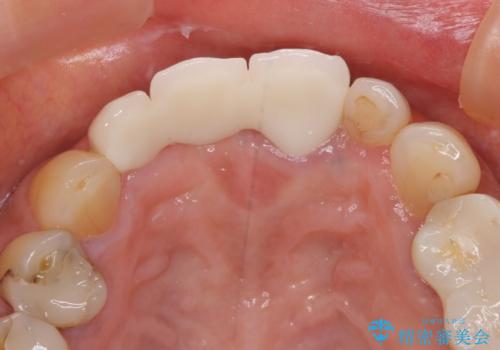

折れてしまった歯は抜歯せざるを得ないため、抜歯と同時に仮歯を装着し、その後オールセラミックブリッジにて補綴することとしました。

折れた前歯を抜歯すると、歯肉が痩せてしまい、ブリッジの形態の審美性が失われることがあります。仮歯を調整することで審美回復が必要であるか判断しますが、今回は歯肉移植を行うことなく補綴治療を行いました。